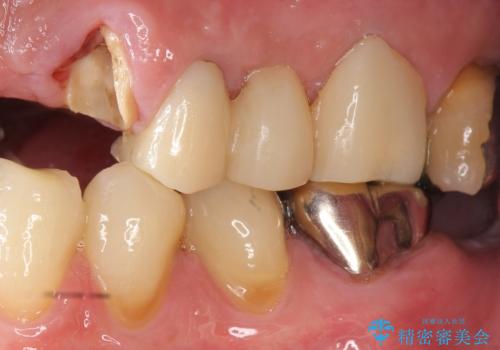

- ブリッジの支台歯であった左上の犬歯が折れたことを主訴に来院された患者様です。

犬歯は歯ぐきの奥深くまで割れており保存不可能な状態でしたが、どうしても抜きたくないとのことでした。

根の長さが短くなるためブリッジの支台歯としては弱いこと、長期的予後は不明なことをご理解頂いた上で治療を行いました。

左上2欠損部の軟組織のボリュームが少なくポンティック部に食渣がたまりやすい歯肉形態であったため、歯槽堤増大術も提案しましたがご希望されませんでした。